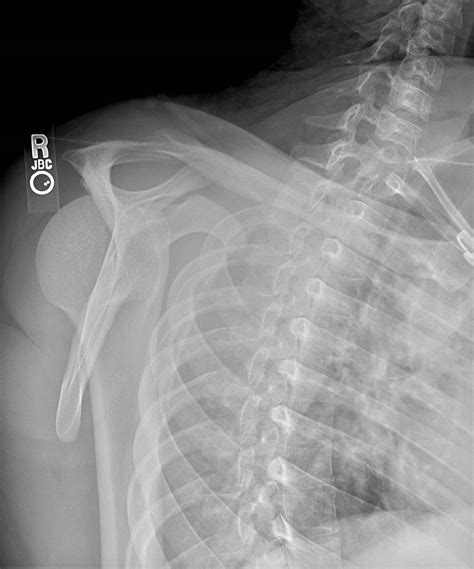

Diagnosing posterior shoulder dislocation involves a combination of physical examination and imaging tests. The diagnostic process typically includes:

• Physical Examination: A healthcare provider will assess the shoulder for deformity, swelling, and range of motion.

• Imaging Tests: X-rays are the primary imaging tool used to confirm the diagnosis. Additional tests such as CT scans or MRIs may be ordered to evaluate the extent of the injury and any associated damage to surrounding tissues.